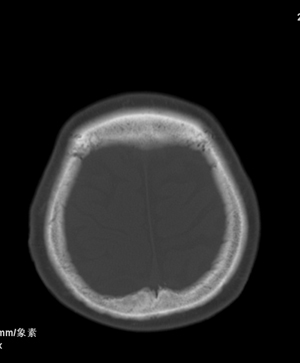

肢体活动肌力均正常。临床印象:脑血管病变。ct意见:脑软化灶,腔梗,请看看枕部病变是脑膜瘤,血管畸形还是其它

颅骨吸收破坏,病灶密度不均,周围见低密度水肿带,多考虑恶性脑膜瘤。

枕骨骨质吸收破坏,局部病灶密度不均,周围见低密度水肿带,考虑脑膜瘤,建议增强扫描。